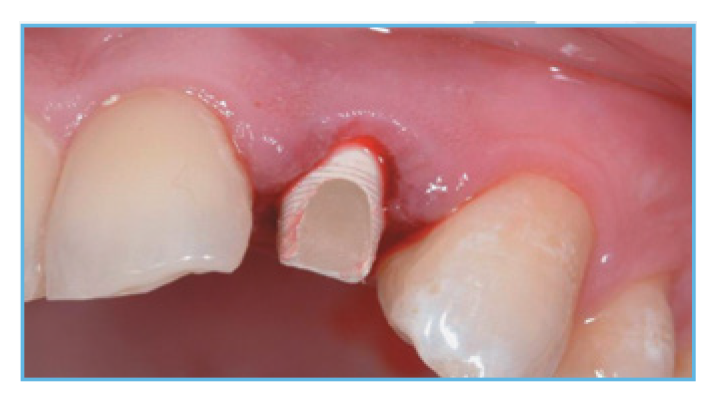

Fig. 3. The PreFormance Post was prepared intraorally to follow the gingival contours.

Fig. 4. The prefabricated crown shell was luted to the PreFormance Post.